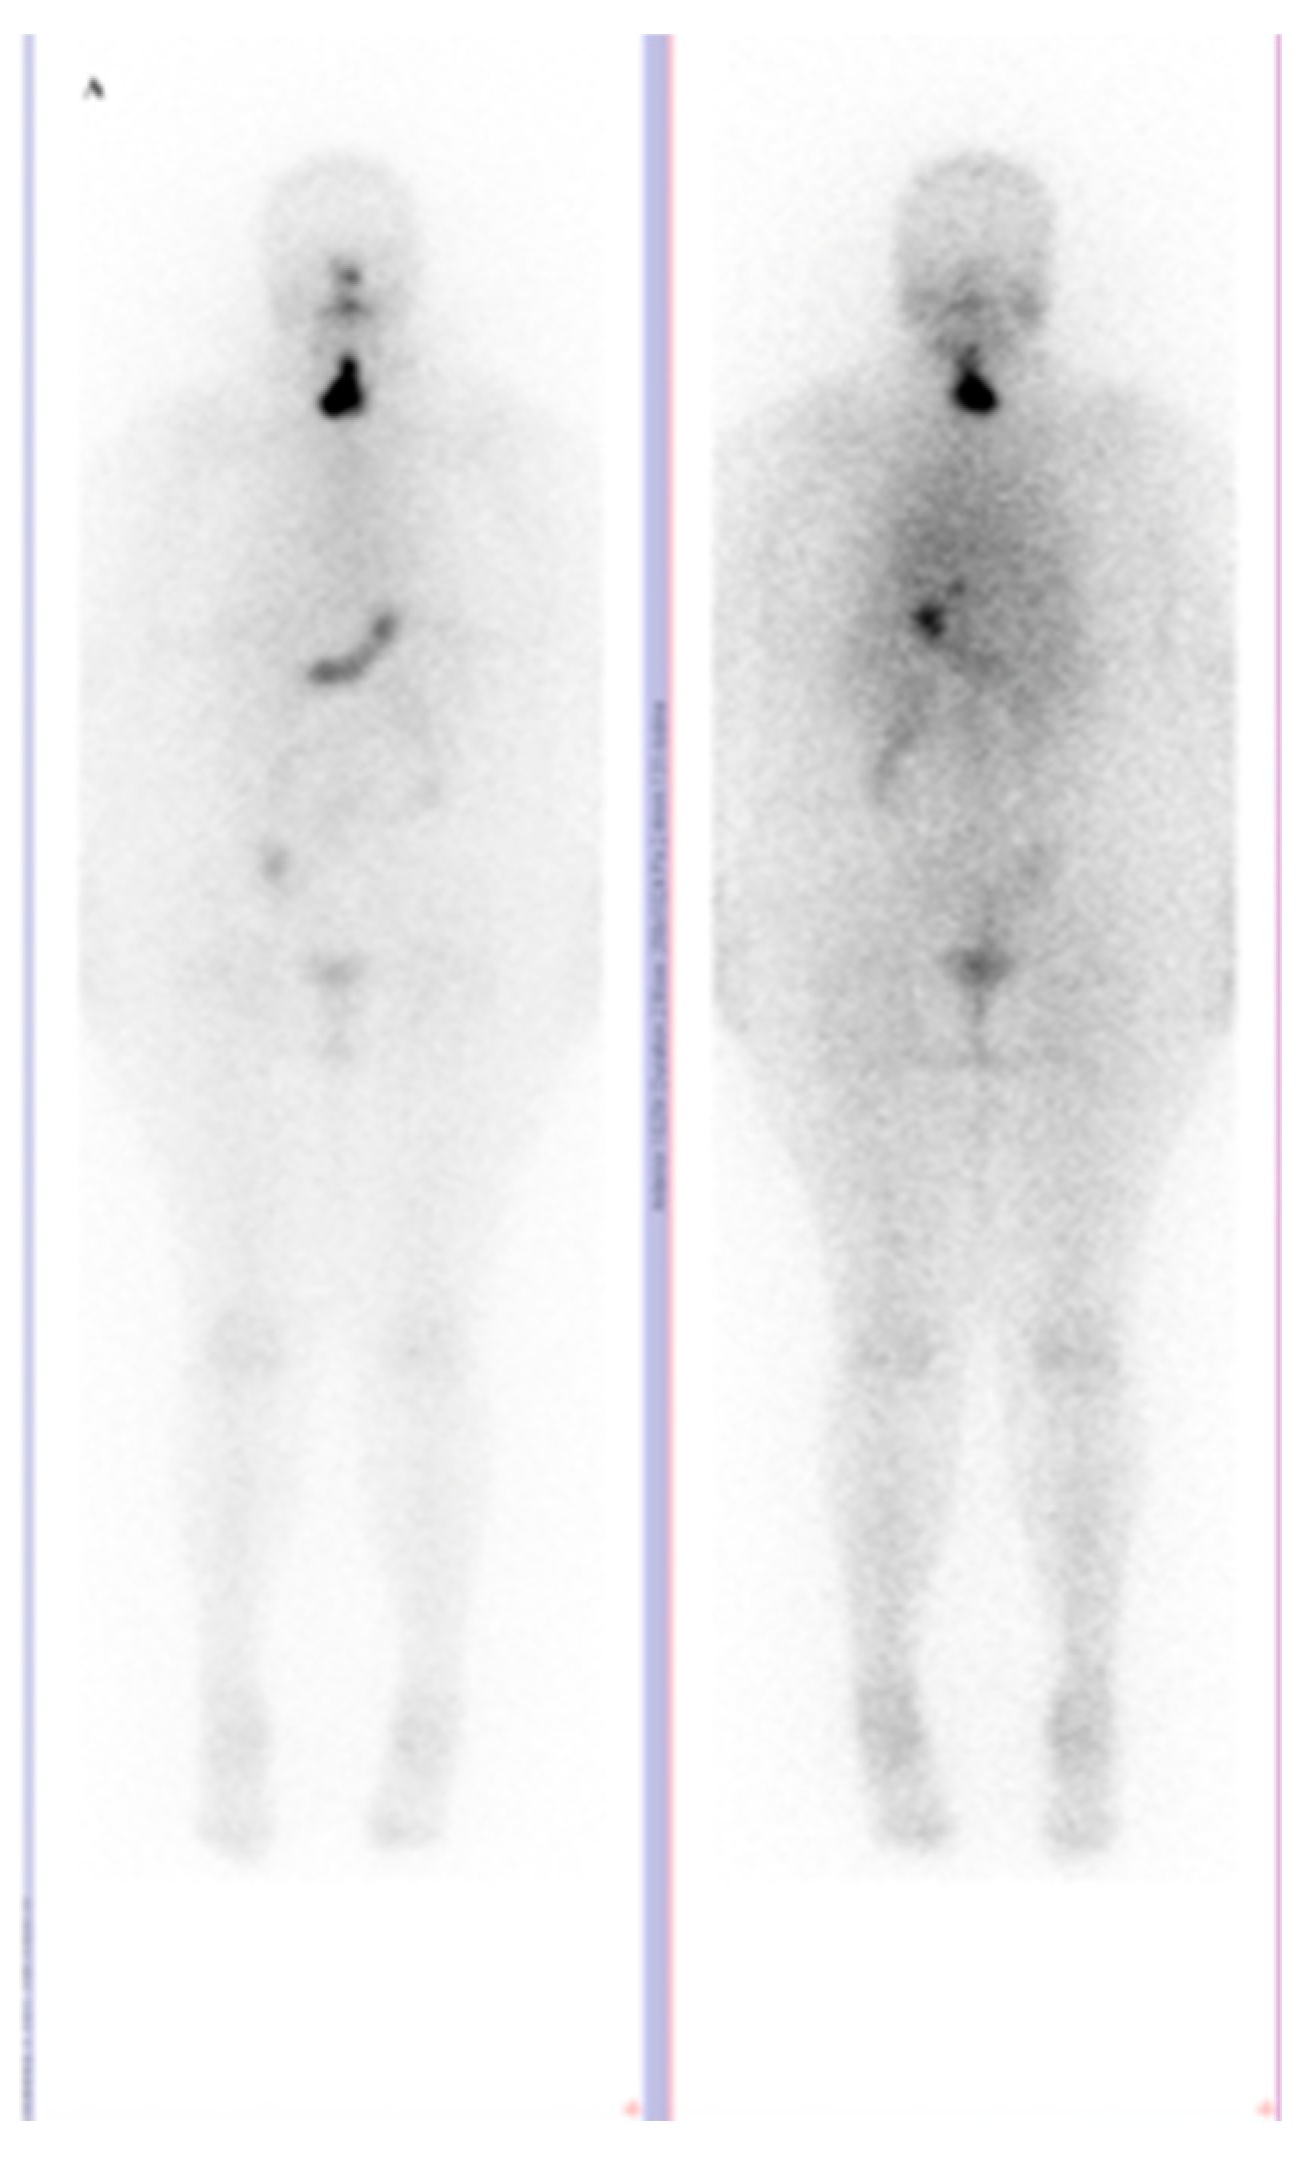

Skeletal Muscle Metastasis in Papillary Thyroid Microcarcinoma Evaluated by F18-FDG PET/CT